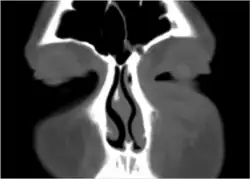

If the diagnosis is unclear, a CT scan may be done to rule out other possibilities.